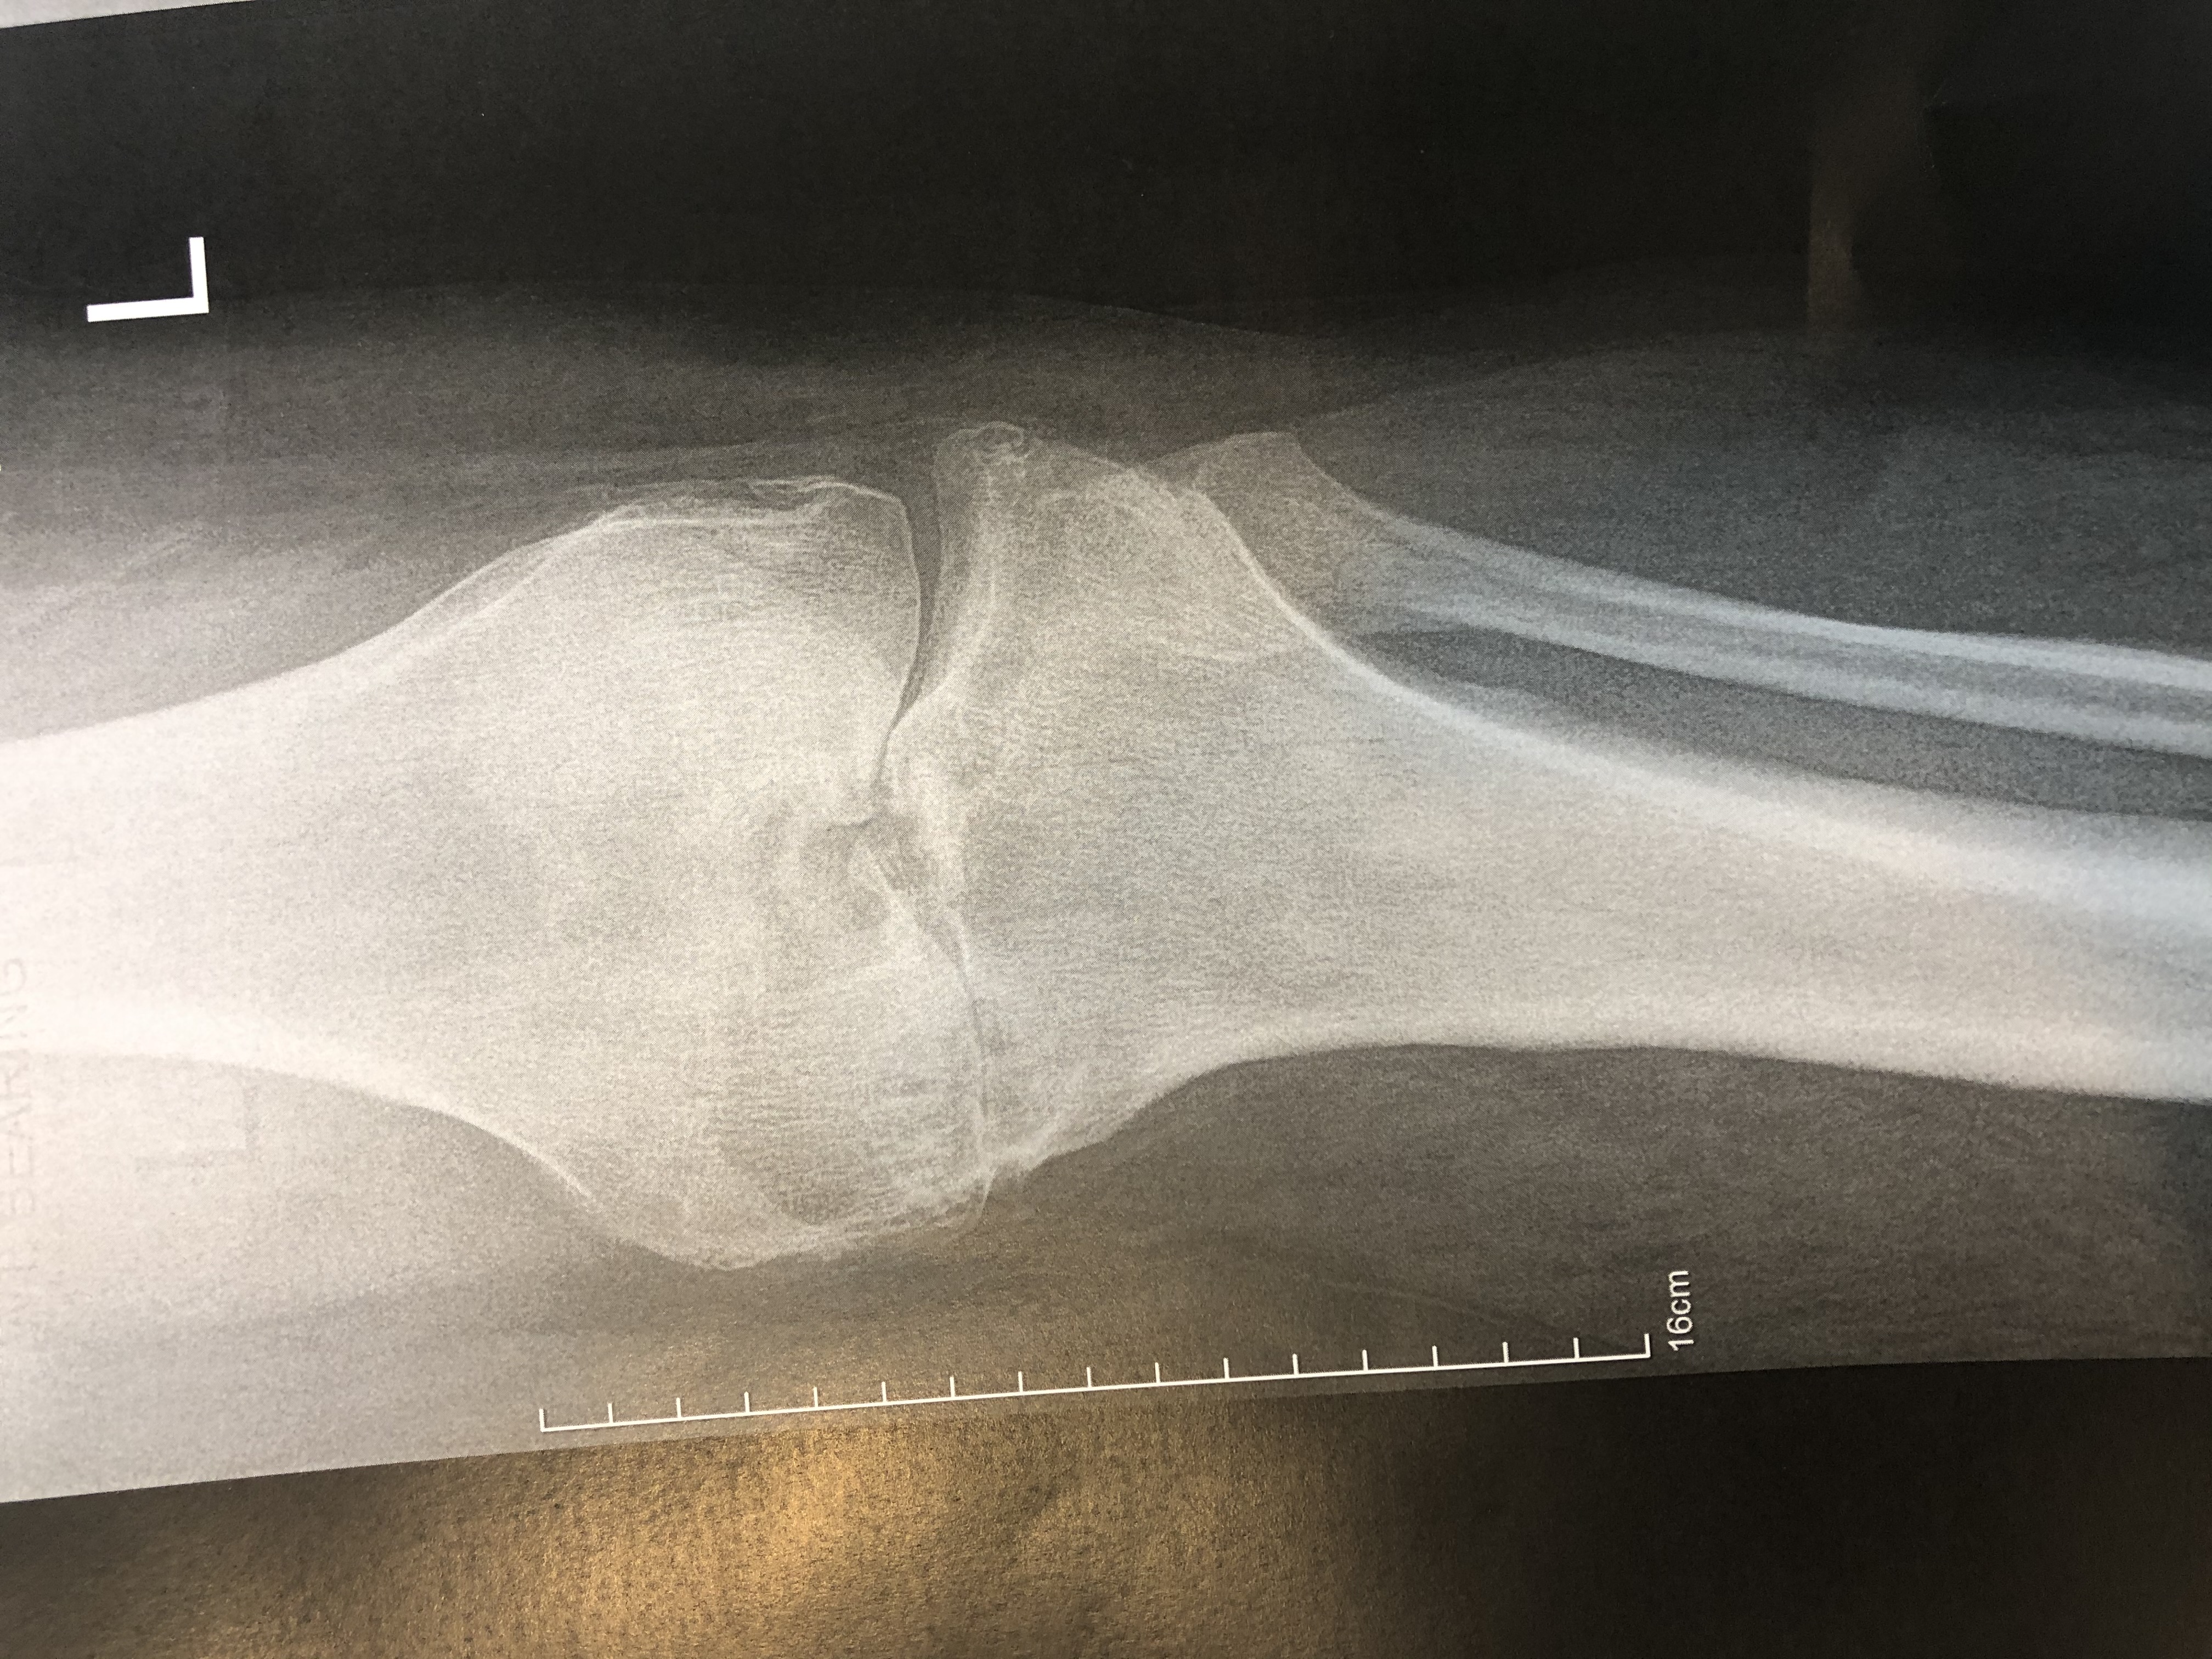

Varus OA Knee Knee Medial OA

Osteoarthritis of the knee, also known as knee OA, is a degenerative joint disease that primarily affects the articular cartilage and surrounding structures in the knee joint. It is the most common form of arthritis and a leading cause of chronic pain and disability among older adults. Knee OA typically develops slowly over time due to the wear and tear on the joint, but it can also occur as a result of previous knee injuries or conditions that affect joint alignment.

In knee OA, the protective cartilage that covers the ends of the bones within the knee joint gradually deteriorates, leading to friction, inflammation, and damage to the underlying bone. This results in pain, stiffness, swelling, and reduced range of motion in the affected knee. As the disease progresses, bone spurs (osteophytes) may develop, further contributing to joint pain and dysfunction.

The diagnosis of knee OA is typically based on a combination of clinical evaluation, medical history, physical examination findings, and imaging studies such as X-rays or MRI scans.